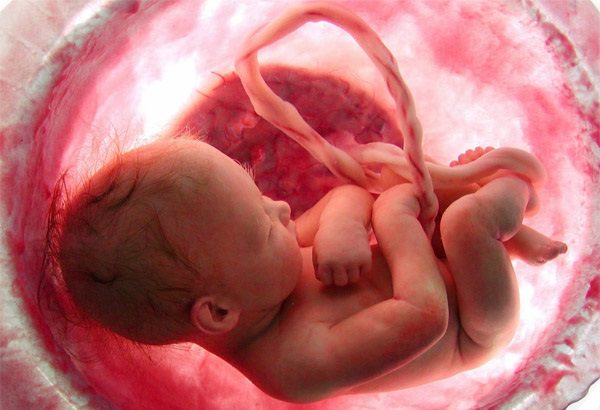

Dị tật thai nhi là những bất thường về hình thái, cấu trúc hoặc chức năng xảy ra trong quá trình phát triển bào thai. Các nguyên nhân phổ biến bao gồm yếu tố di truyền, môi trường và các bệnh lý của mẹ.

Dị tật bẩm sinh có thể xảy ra do nhiều nguyên nhân, từ yếu tố di truyền, môi trường đến những thay đổi bất thường trong quá trình phát triển của thai nhi. Việc hiểu rõ các loại dị tật phổ biến không chỉ giúp mẹ bầu có cái nhìn toàn diện hơn mà còn hỗ trợ trong việc theo dõi sức khỏe thai kỳ và phát hiện sớm những bất thường.